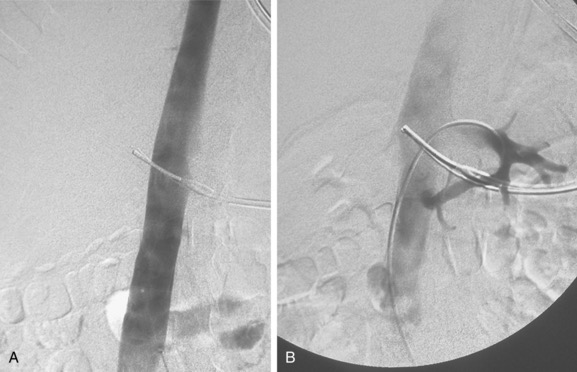

• پوست با مواد ضدعفونی تمیز میشود، بیحسی موضعی تزریق میشود و برش کوچکی (کمتر از ۱ سانتیمتر) ایجاد میشود. - قرار دادن وایر راهنما (guidewire):

• با سوزن، ورید پانکچر میشود (اغلب تحت اولتراسوند برای دقت).

• وایر نازک وارد ورید میشود و تحت فلوروسکوپی به IVC هدایت میشود. - ونوگرافی (Cavography):

• کاتتر چندسوره وارد میشود.

• ماده حاجب تزریق میشود تا آناتومی IVC، قطر آن، موقعیت وریدهای کلیوی (renal veins) و وجود لخته بررسی شود.

• موقعیت ایدهآل فیلتر: درست زیر وریدهای کلیوی (infrarenal) برای جلوگیری از انسداد

- قرار دادن sheath تحویل فیلتر ivc قلبی:

• sheath (لوله بزرگتر) روی وایر پیشرفته میشود تا به موقعیت مورد نظر برسد. - باز کردن (Deployment) فیلتر ivc قلبی:

• فیلتر فشردهشده داخل sheath推進 میشود.

• sheath عقب کشیده میشود تا فیلتر باز شود و با قلابها یا پاها به دیواره IVC بچسبد.